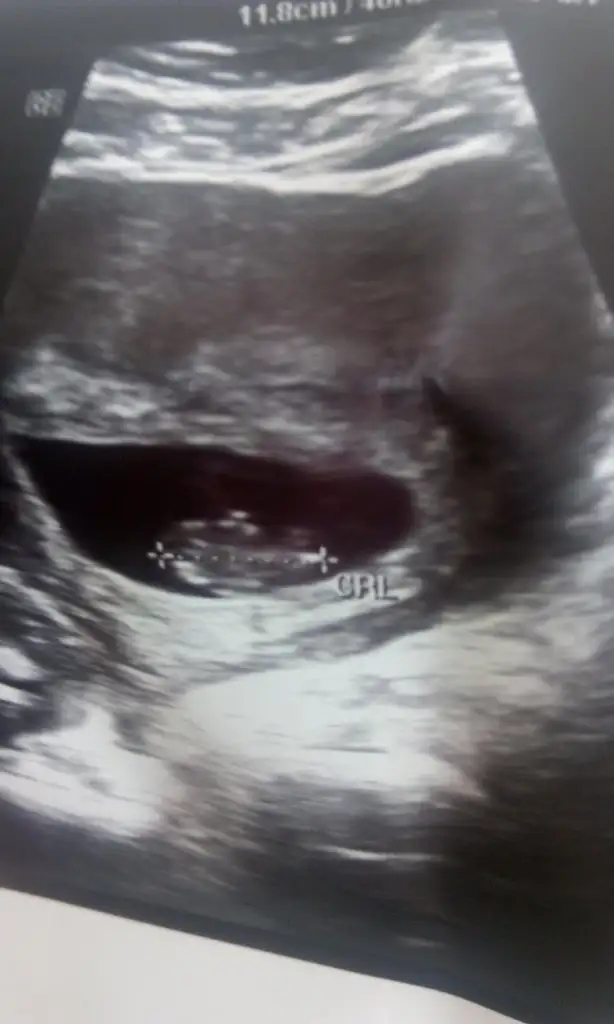

Bebişimmm hadi gördün minnoşunuda bende çok merak ediyorum gidemedim daha

Kolayda usg fotoğrafını koyar mısın :)

canım benim göreli çok oldu.iki haftadan çok.crazybele yazdım.benim ki daha minnak en son usg de 7. haftadaydık teyzesi o zaman bak böyle iki hafta sonra yeni halini paylaşırım canım.

canım benim göreli çok oldu.iki haftadan çok.crazybele yazdım.benim ki daha minnak en son usg de 7. haftadaydık teyzesi o zaman bak böyle iki hafta sonra yeni halini paylaşırım canım. Eki Görüntüle 1548375

Oyyy kıyamamm yaaa teyzesi yesin onu Bende meraktan çatlıyorum bir randevumu kaçırdım diğerinde grev vardı taa 12.de gidicem Tam bir ay olacak o zaman çatlıyorum meraktan

bizde seni öperiz teyzesi mis bebek kokulu hemde ben zaten ayda bir gidiyorum canım.dr bir ay sonra gel dedi.20-25 i gibi bekliyorum dedi ama eşim sabredemiyor 15 in de gidelim mi diyor bende çok merak ediyorum